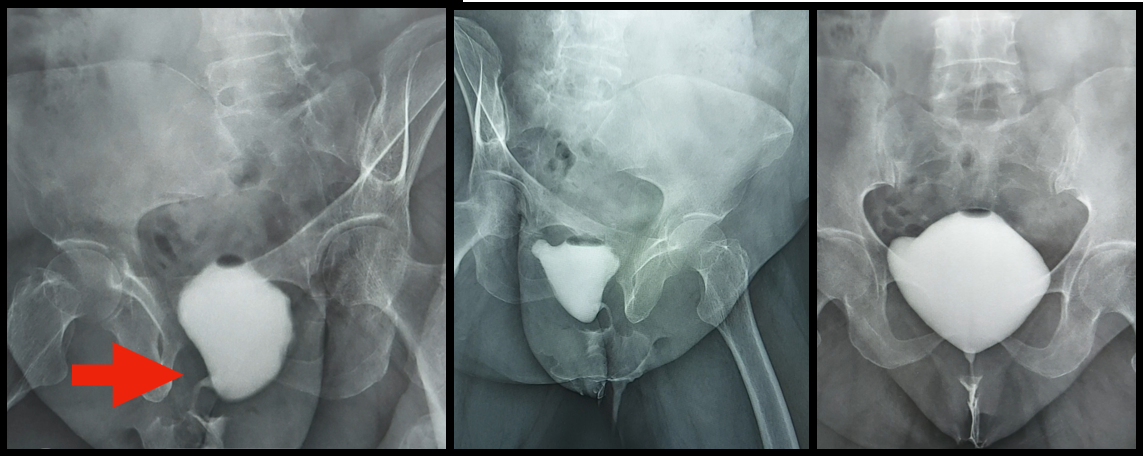

Figures 2A ,2B, 2C

Figure 2: MCU image A) right oblique B) left oblique C) anteroposterior. Red arrow shows kinking of urethra and cystocoele.

I don’t think the MCUG is abnormal. The urethra is wide open during voiding and her bladder neck triangulated beautifully during voiding and you said she has no PVR. Yes, there is a bit of a curve, but it is an oblique view, and the cystocele may have distorted it a little. It is definitely not the appearance of obstruction like with a tight sling or detrusor-external sphincter dyssynergia (DESD), and there is no proximal dilation. So, I would not worry about the so-called ‘kinking’ on the radiology report. It is not obstructed and none of her history and findings support obstruction.

I would remove the catheter and continue her on low dose antibiotics for the moment. I would also continue the vaginal estrogen cream. It is hard to know what to make of the “kinked” urethra. Typically, stage one anterior vaginal wall prolapse will not impact voiding to a large degree. However, on the MCU it appears the prolapse may be more significant. One option would be to reexamine her perhaps in more of a standing position and possibly offer her a pessary trial and see if her symptoms continue to improve – off the low dose antibiotics. If they do, you could then consider an operative repair or maintain the pessary. If not, restart the low dose antibiotics and consider a pelvic MRI to make sure there is not a urethral diverticulum that did not show up on MCU.